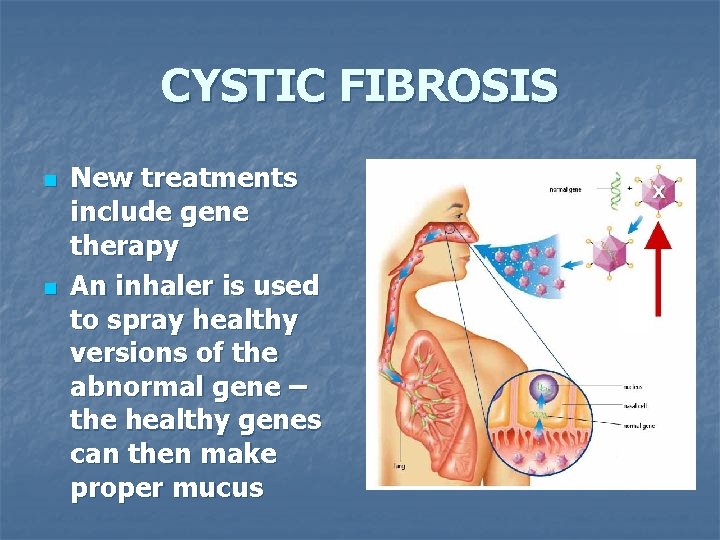

CYSTIC FIBROSIS n n New treatments include gene therapy An inhaler is used to spray healthy versions of the abnormal gene – the healthy genes can then make proper mucus